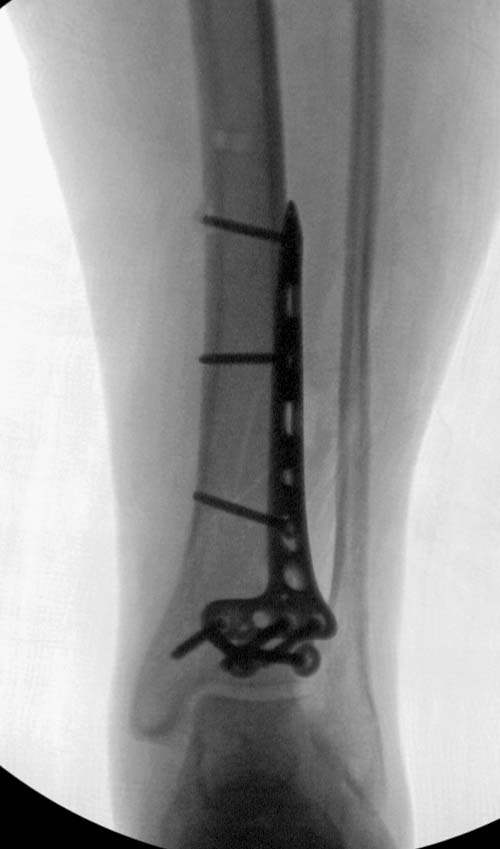

Первый случай, где перелом в результате падения с небольшой высоты, где мортиз рентген снимок показал отстутствие укорочения наружной

лодыжки и КТ срезы подсказали направления атаки. После такой фиксации нет надобности в гипсовой повязке, брейс и через две недели движения в

суставе без нагрузки.